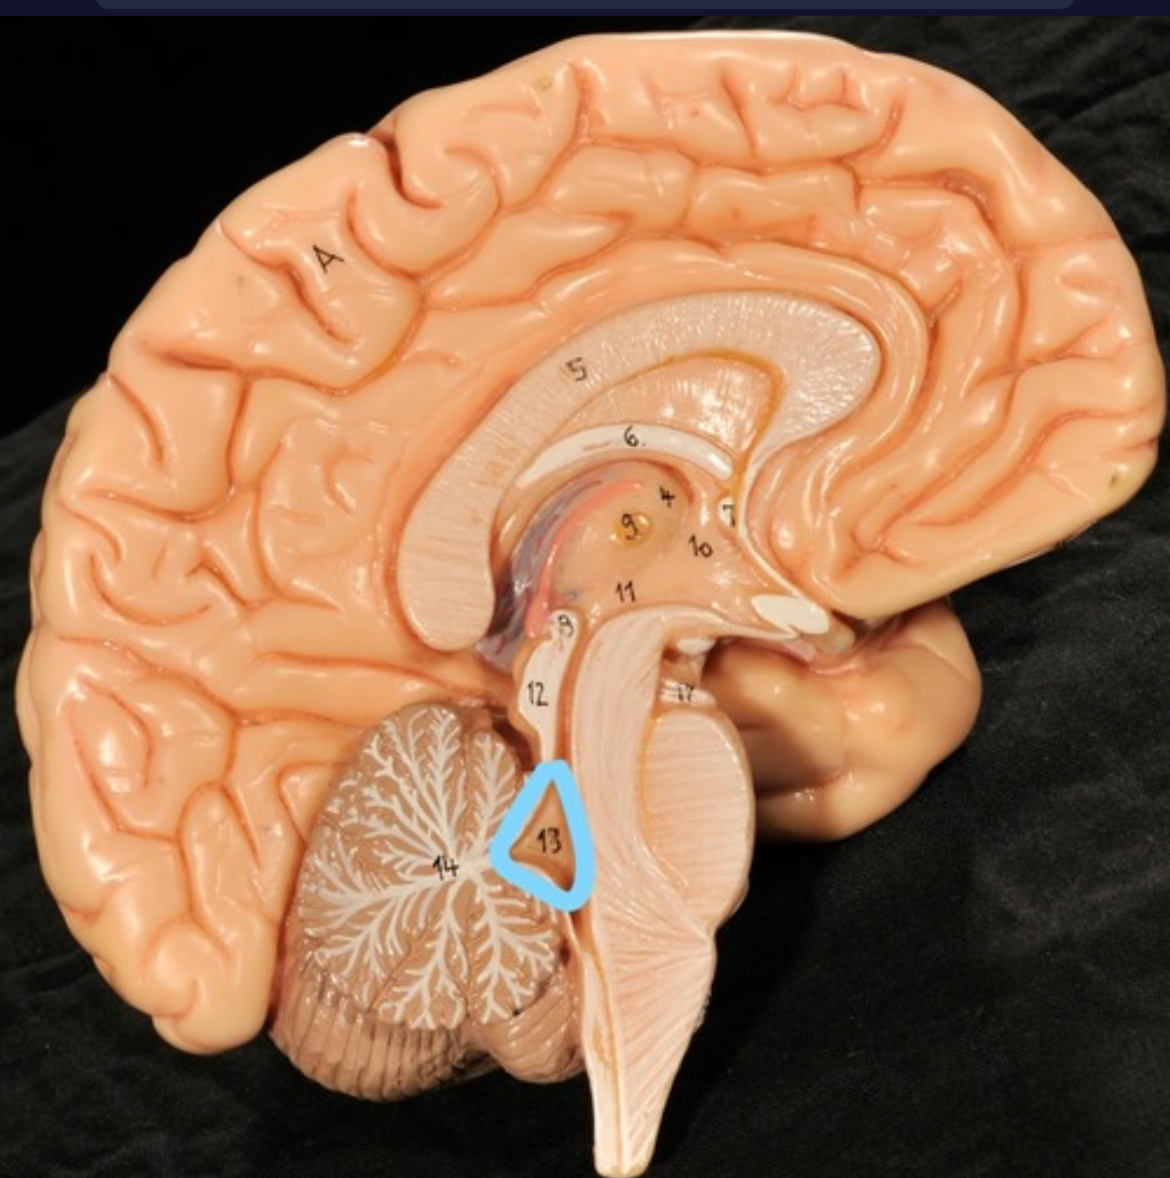

Cerebellum

Pons

Medulla oblongata

4th ventricle

central canal